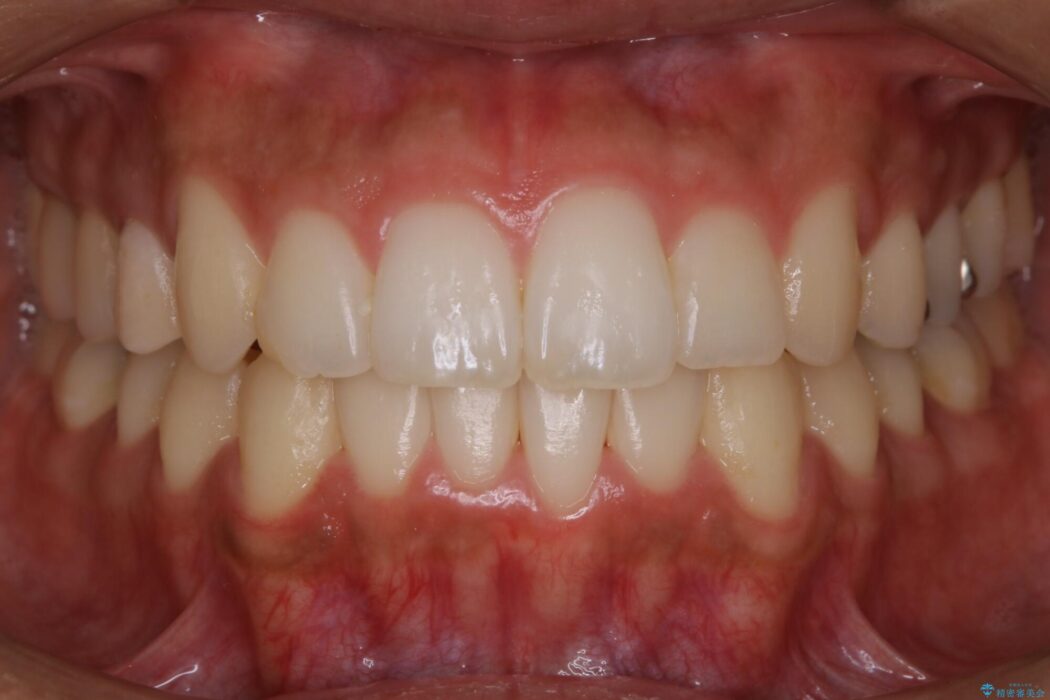

【20代男性】出っ歯をインビザラインで矯正治療

歯列のガタガタと飛び出ている前歯を治したいとのことで来院されました。